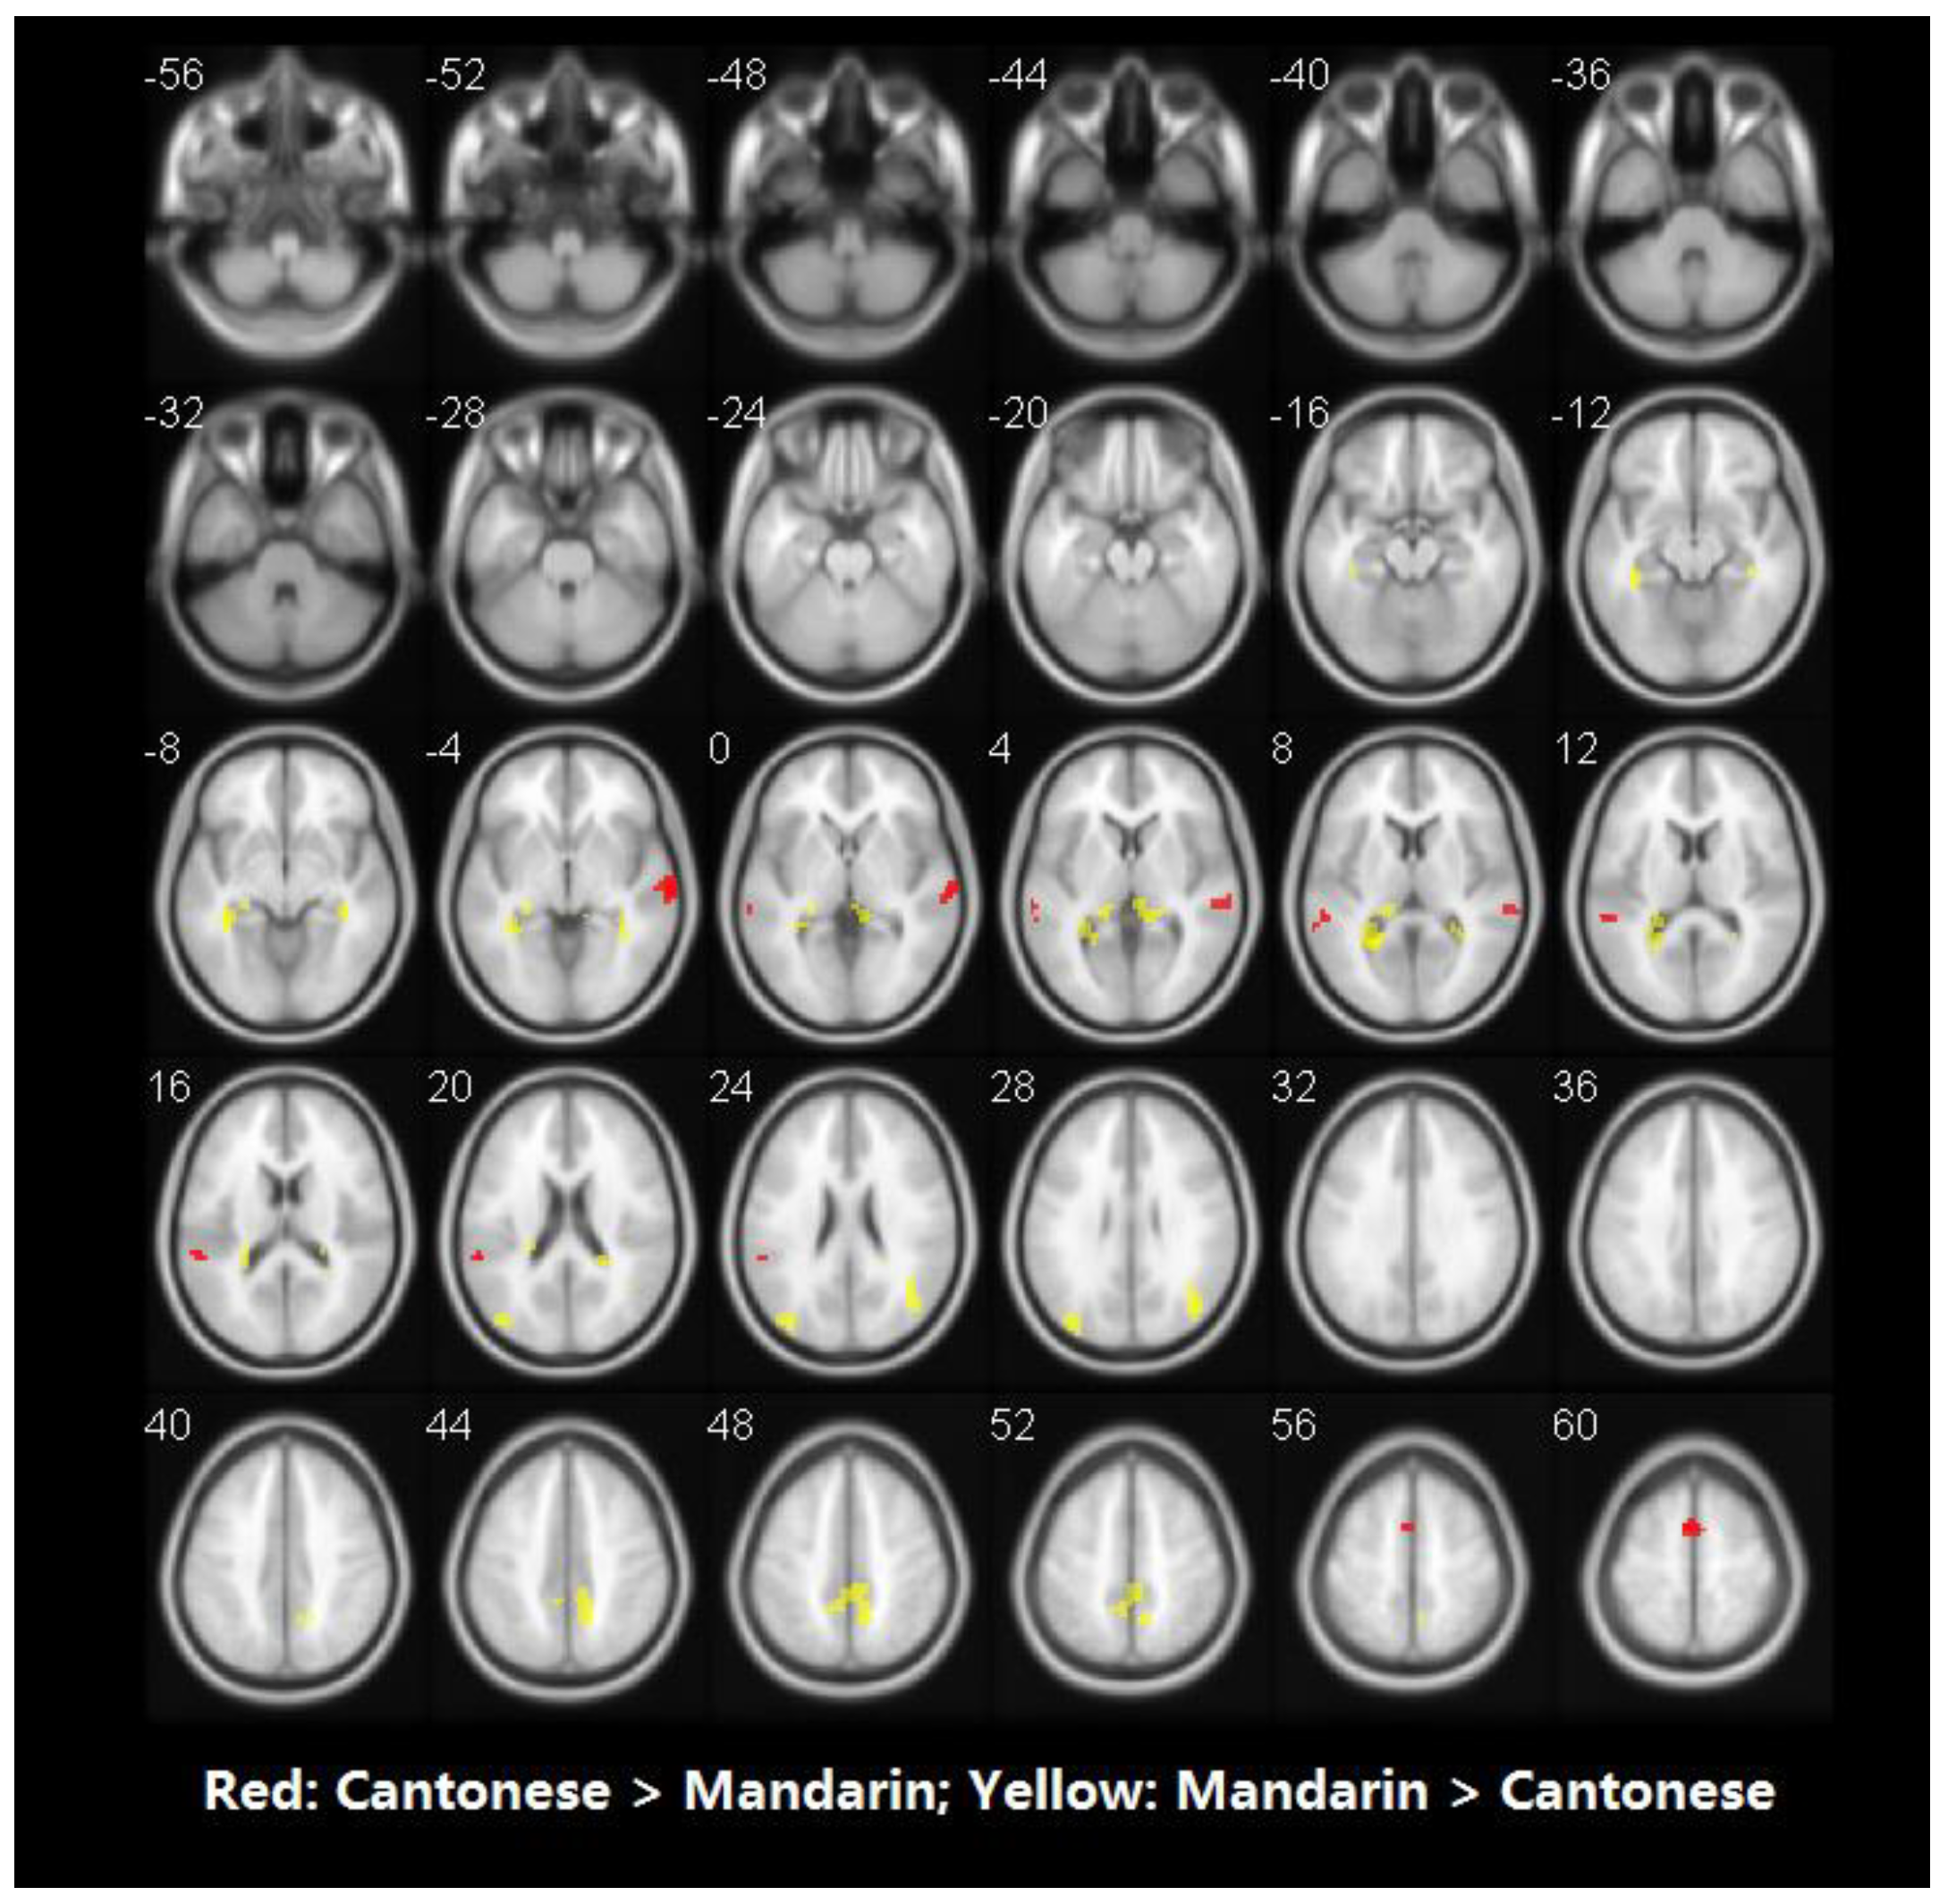

Table 5 presents brain activity patterns for each language separately for the auditory word rhyming task. Table 6 and Figure 5 shows the results of the group comparisons. Pairwise comparisons between the three languages indicated that: (1) compared to Mandarin processing, Cantonese processing produced greater activity in the bilateral posterior superior temporal gyri (STG), and the left supplementary motor area (SMA). Conversely, Mandarin processing induced greater activity in bilateral middle occipital gyri (MOG), left calcarine sulcus, right hippocampal gyrus, parahippocampal gyrus, and precuneus. (2) No significant differences in brain activity were observed between Cantonese and English processing.

Similarity analyses indicated that there was 0.967 similarity between Cantonese and Mandarin, and 1.000 between Cantonese and English (Figure 6).

In the auditory modality, compared to Cantonese, Cantonese-native-speaking subjects used different brain regions to process Mandarin but used similar brain regions to process English. Brain activities underpinning the phonological processing of Mandarin were more widespread compared to those of Cantonese. When compared to Mandarin, the phonological processing of Cantonese generated greater activity in the bilateral posterior STG and left SMA, while compared to Cantonese, the phonological processing of Mandarin generated greater activity in bilateral MOG, left calcarine sulcus, right hippocampal gyrus, parahippocampal gyrus, and precuneus. There is no relevant neuroimaging literature on Chinese bilinguals with regard to auditory word processing at present. Jung et al. [49] examined the brain activity of Korean–English bilinguals during auditory phonological processing and reported that L2 English processing evoked more widespread and stronger activation compared to L1 Korean processing, consistent with our findings that L2 Mandarin evoked more widespread brain regions than L1 Cantonese in auditory word rhyming tasks.